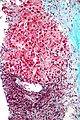

Micrograph showing a Mallory body with the characteristic twisted-rope appearance (centre of image - within a ballooning hepatocyte). H&E stain.

Mallory bodies are highly eosinophilic and thus appear pink on H&E stain. The bodies themselves are made up of intermediate cytokeratin 8/18 filament proteins that have been ubiquinated, or bound by other proteins such as heat shock proteins, or p62/Sequestosome 1.[5]